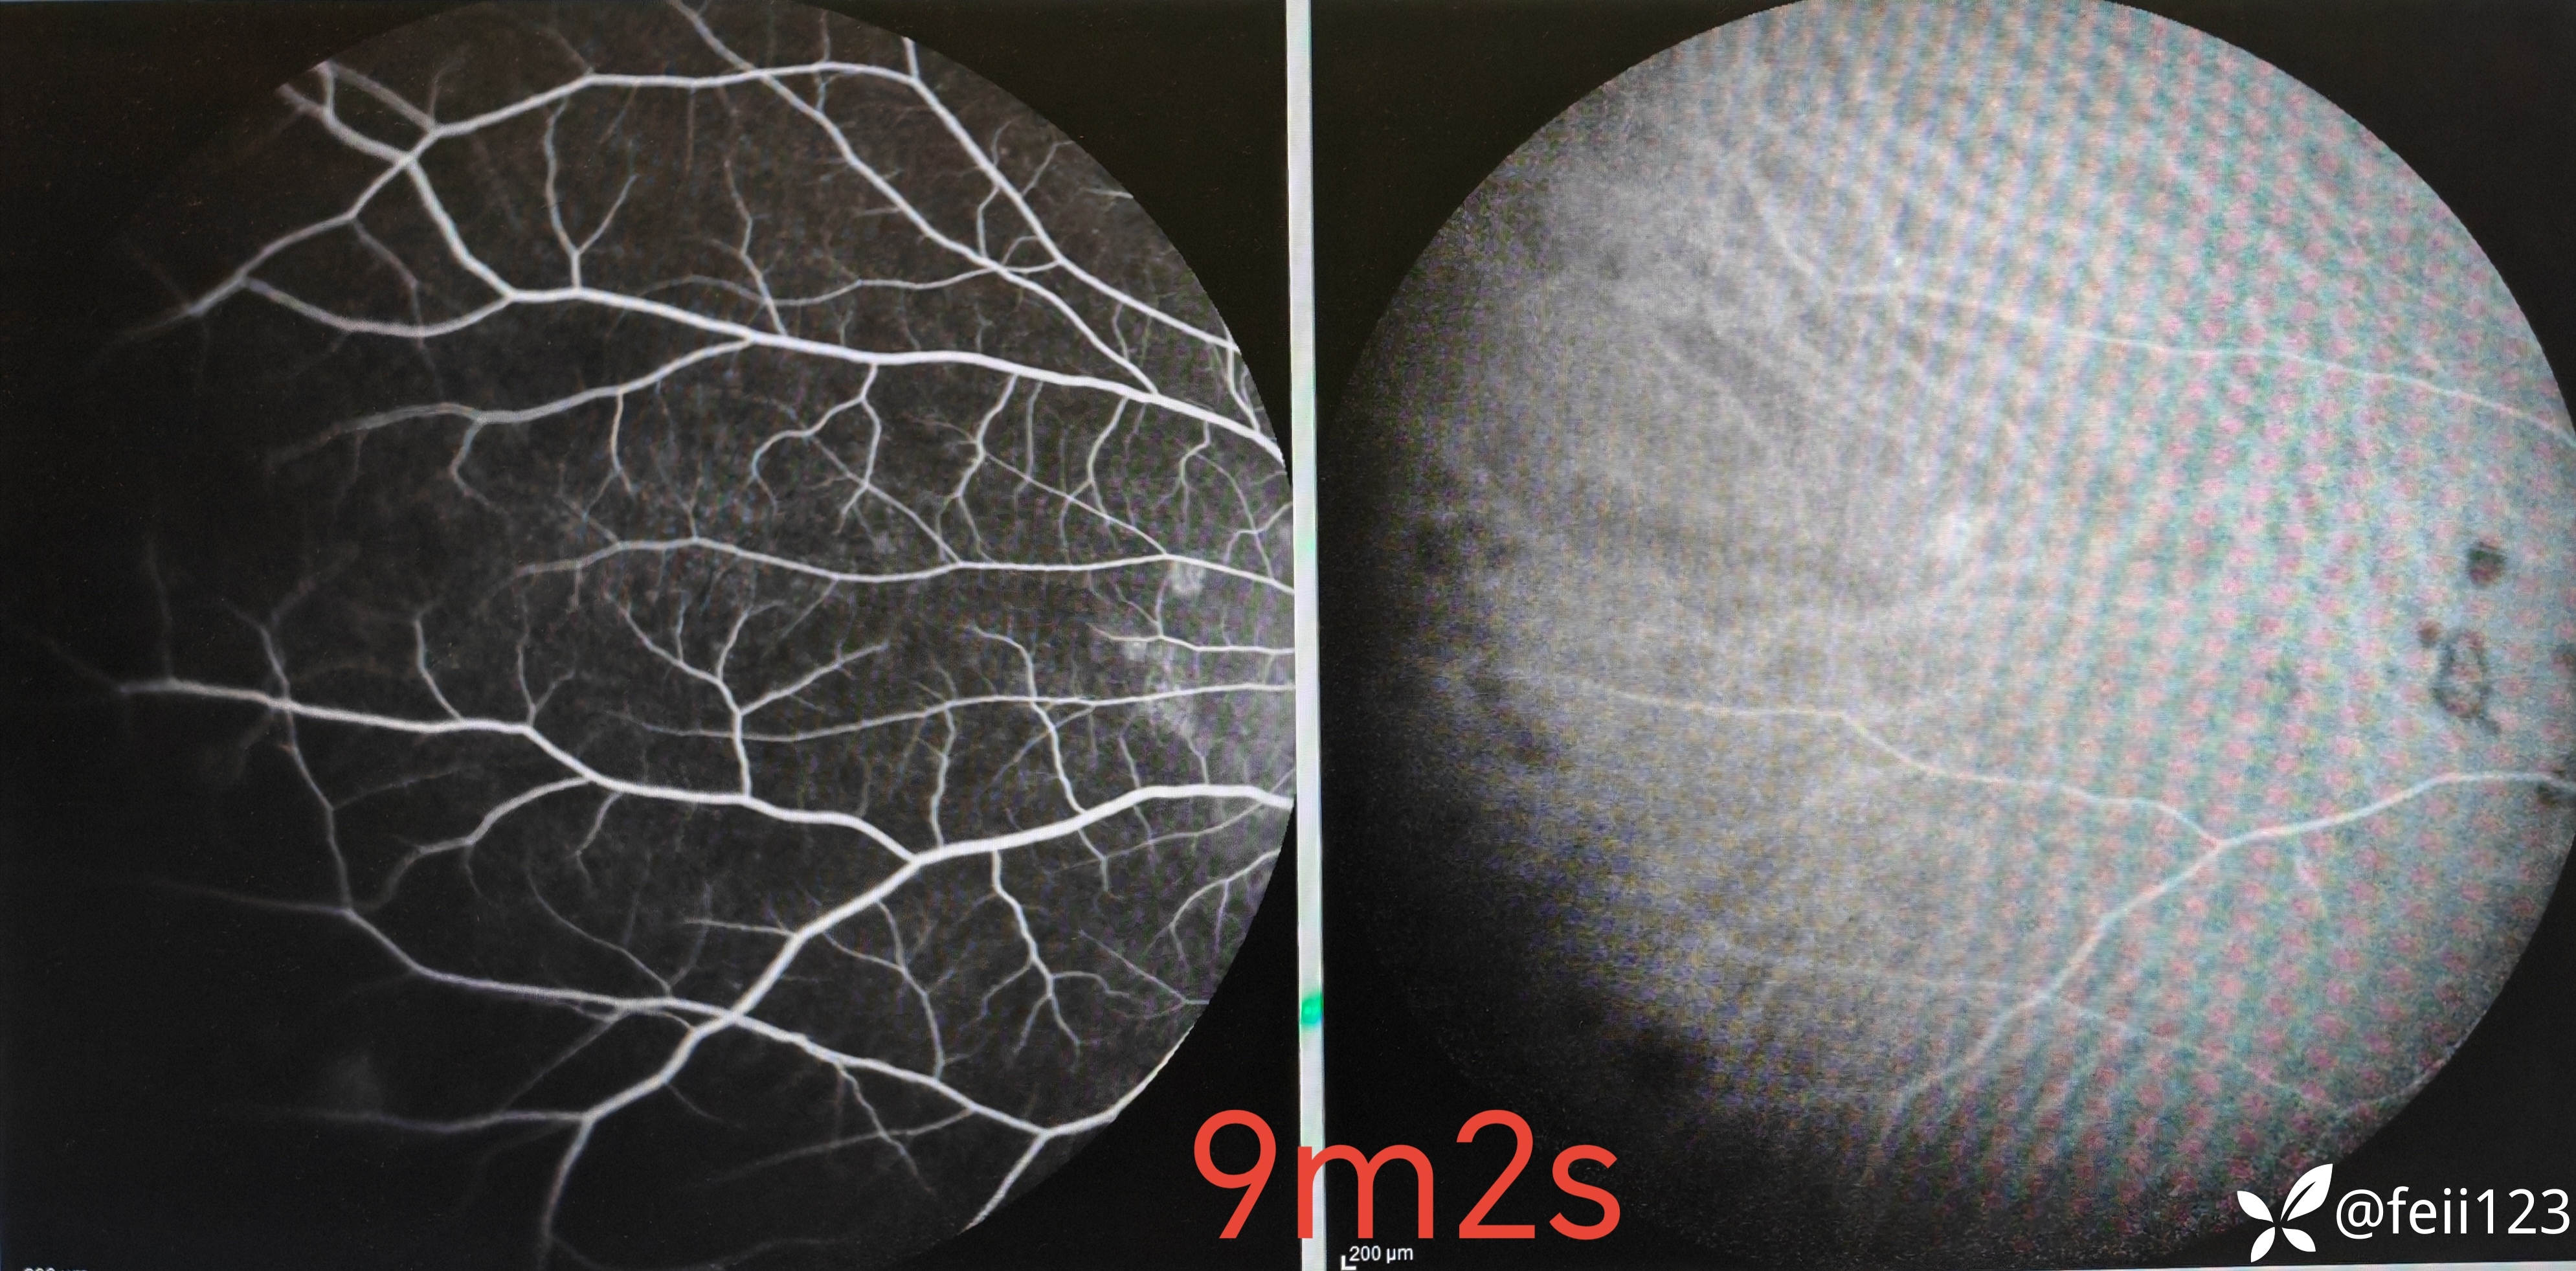

患者信息】:年轻男性30岁

【主诉】:左眼前黑点5天,无诉闪光感

【现病史及既往史】:无特殊,无全身病,中高度近视史

【检查】矫正视力右眼1.0左眼0.4,眼压正常15 16,眼前段未见异常,玻璃体清,眼底如图,左眼底可见后极部及鼻侧周边多个白点。